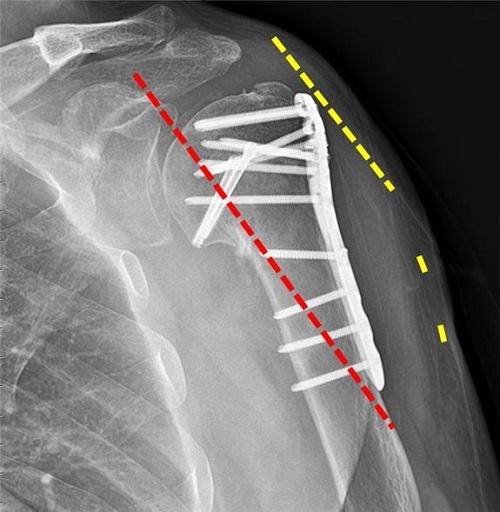

어깨뼈 골절 수술 후, 입원 중에는 주로 진통제가 투여되어 통증을 관리합니다. 이로써 입원 중에는 통증이 그리 심하지 않게 느껴질 수 있습니다. 상완골 골절의 경우 핀고정 수술이 주로 시행되며, 수술 후에는 상완골의 고정이 유지됩니다.

어깨뼈 골절 수술 후, 본격적인 물리치료 및 재활치료가 시작됩니다. 이때까지 깁스 등의 고정 상태가 유지되었지만, 이제부터는 근육과 관절을 복원하고 활동성을 회복하기 위한 치료가 중요합니다. 물리치료와 재활치료는 통증 경감 뿐만 아니라 움직임의 범위를 늘리고 근력을 향상시키는 데 도움을 줍니다.

물리치료와 재활치료는 개인의 상태와 의사의 지시에 따라 다양한 운동 및 치료 방법을 포함합니다. 이러한 치료는 수술 후 약 4주 정도부터 시작됩니다.